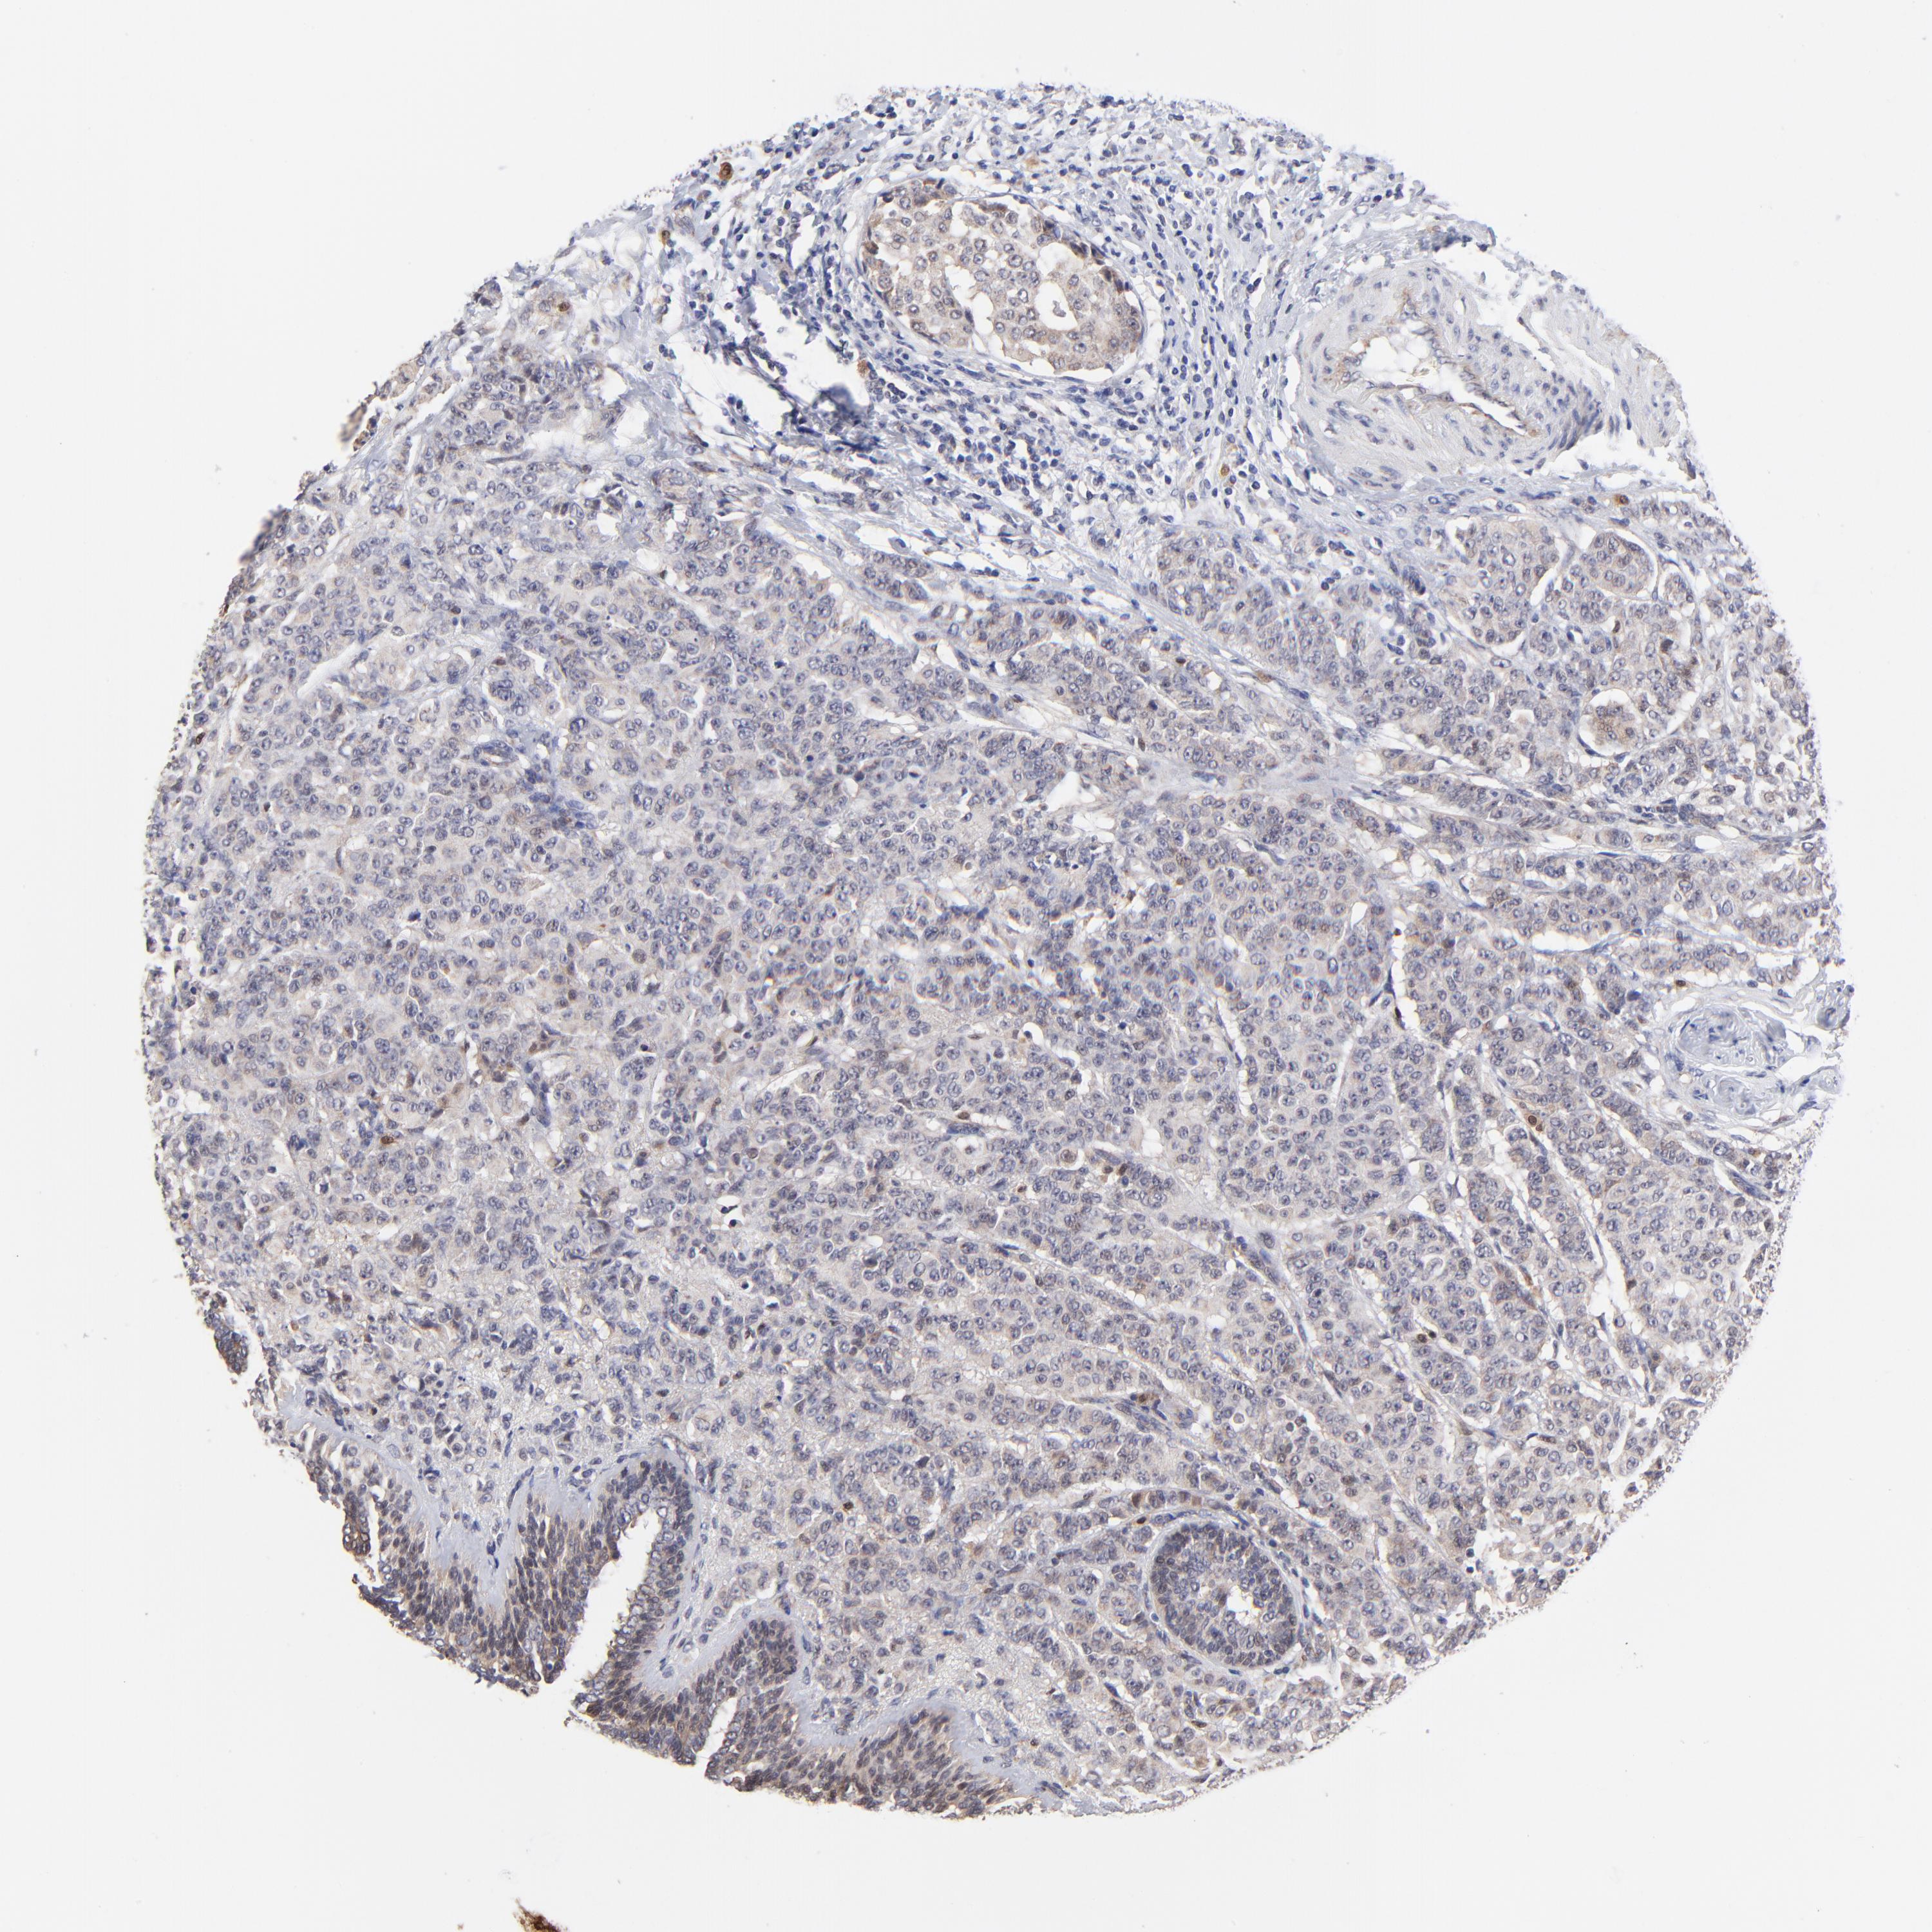

BRCA TCGA BRCA VALIDATION PROTEIN EXPRESSION

Breast cancer

Human cancer